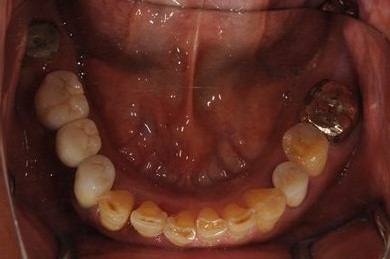

インプラントの症例写真 IMPLANT

骨再生インプラント治療

| 治療方針 | 右上奥はソケットリフトにて上顎洞拳上してインプラント埋入を可能にし、上顎前歯部は骨再生法によりインプラント治療を行う。その他、補綴により口腔内全体の機能的審美的回復を行う。 | ||||||||||||||||||||||||||||||||

| 治療内容 | インプラント8本(GBR、ソケットリフト)、ハイブリッドセラミッククラウン17本(セラミック用土台5本) | ||||||||||||||||||||||||||||||||